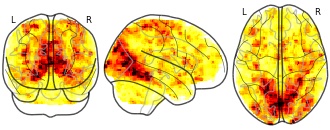

"name": "VBM_HeterogeneityMap",

"description": "Abnormal gray matter in BPD. Brain regions with significant heterogeneity (i.e. between-study variance) in the comparison of patients with BPD and healthy controls. Results are thresholded at at p<.005 & k>20. Note: Results are based on meta-analysis of group comparisons. Note2: Results were updated (see Erratum for this publication)",

"add_date": "2016-01-21T18:23:32.131003+01:00",